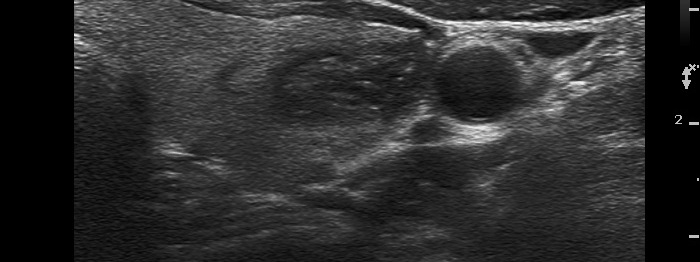

Follicular adenoma (histological diagnosis)

After aspiration of 2 mL cystic fluid |

It became more evident after removal of the cystic fluid that the figures are comet-tail artifacts.